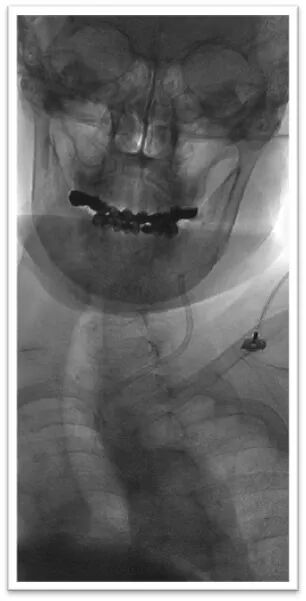

图4:DSA提示主动脉弓为牛角弓,左侧颈总动脉发自头臂干动脉,右侧颈内动脉造影提示前交通动脉开放,呈双干大脑前动脉,左侧大脑前动脉通过软膜支向左侧大脑中动脉供血区域代偿,双侧椎动脉均势供血,左侧大脑后动脉通过软膜支向前代偿供血;左侧颈总动脉闭塞,残端呈杯口状,近端可见白色血栓影,初步考虑栓塞性闭塞。

患者既往高血压病病史,目前诊断为左侧颈总动脉闭塞性脑梗死(心源性栓塞),闭塞机制考虑心脏内血栓或赘生物脱落堵塞颈动脉血管,经多模影像评估存在明显不匹配区,符合DAWN研究入组条件,拟急诊局麻下行颈总动脉开通术。